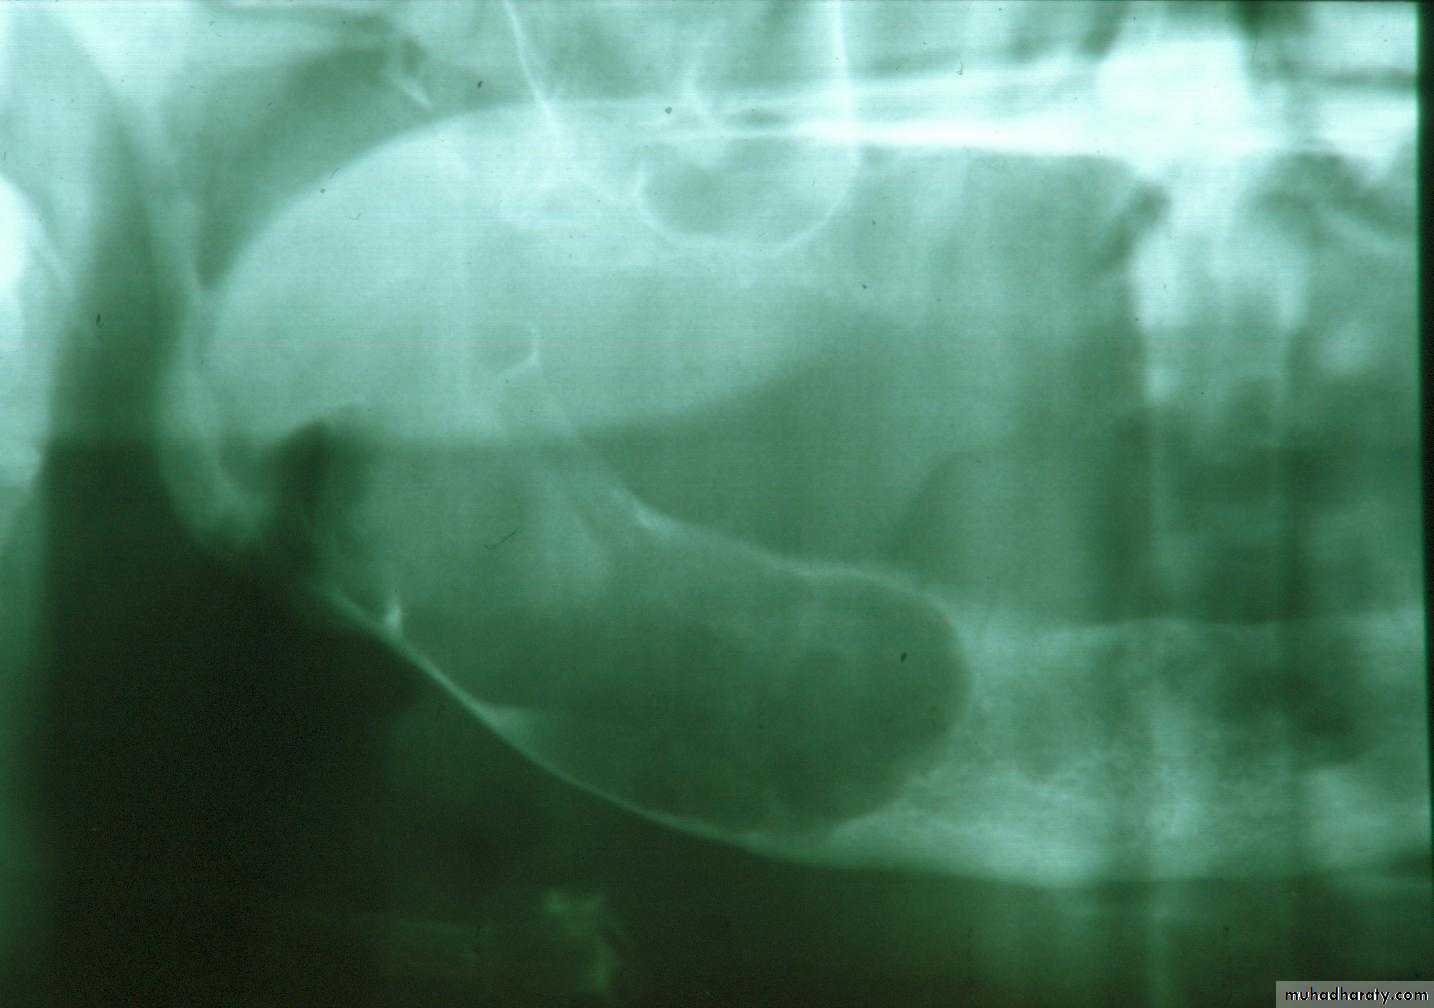

f. Vestibuloplasty: ridge extension … move muscle attachment and retain with soft tissue graftPreprosthetic Surgery

f. Vestibuloplasty: move muscle attachment and retain with soft tissue graft

f. Vestibuloplasty: Maxillary palatal graft vestibuloplastyf. Bone grafting: